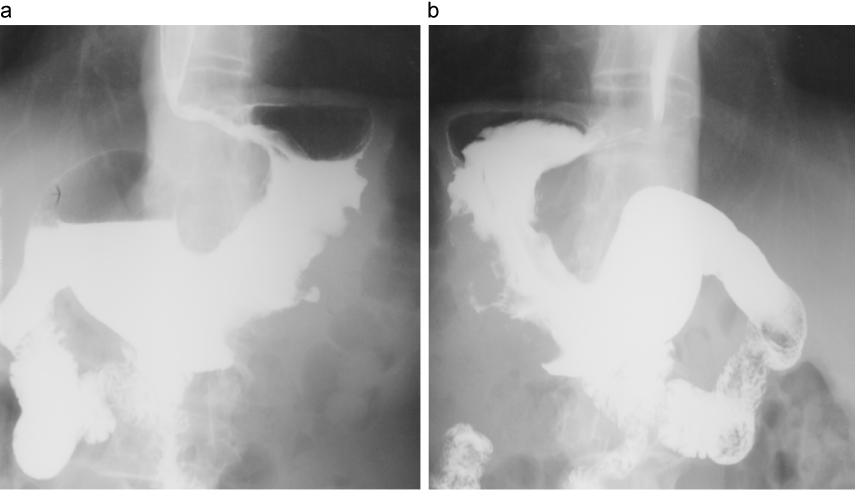

上部消化管造影検査

img

1: 小寺泰弘先生ご提供

スキルス胃癌の上部消化管造影所見

出典